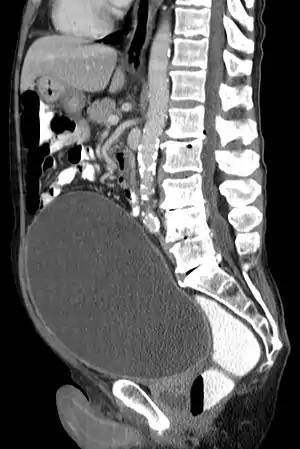

| Urinary retention with greatly enlarged bladder as seen by CT scan. | |

Analysis of urine flow may aid in establishing the type of micturition (urination) abnormality. Common findings, determined by ultrasound of the bladder, include a slow rate of flow, intermittent flow, and a large amount of urine retained in the bladder after urination. A normal test result should be 20-25 mL/s peak flow rate. A post-void residual urine greater than 50 ml is a significant amount of urine and increases the potential for recurring urinary tract infections. In adults older than 60 years, 50-100 ml of residual urine may remain after each voiding because of the decreased contractility of the detrusor muscle.[5] In chronic retention, ultrasound of the bladder may show massive increase in bladder capacity (normal capacity is 400-600 ml).